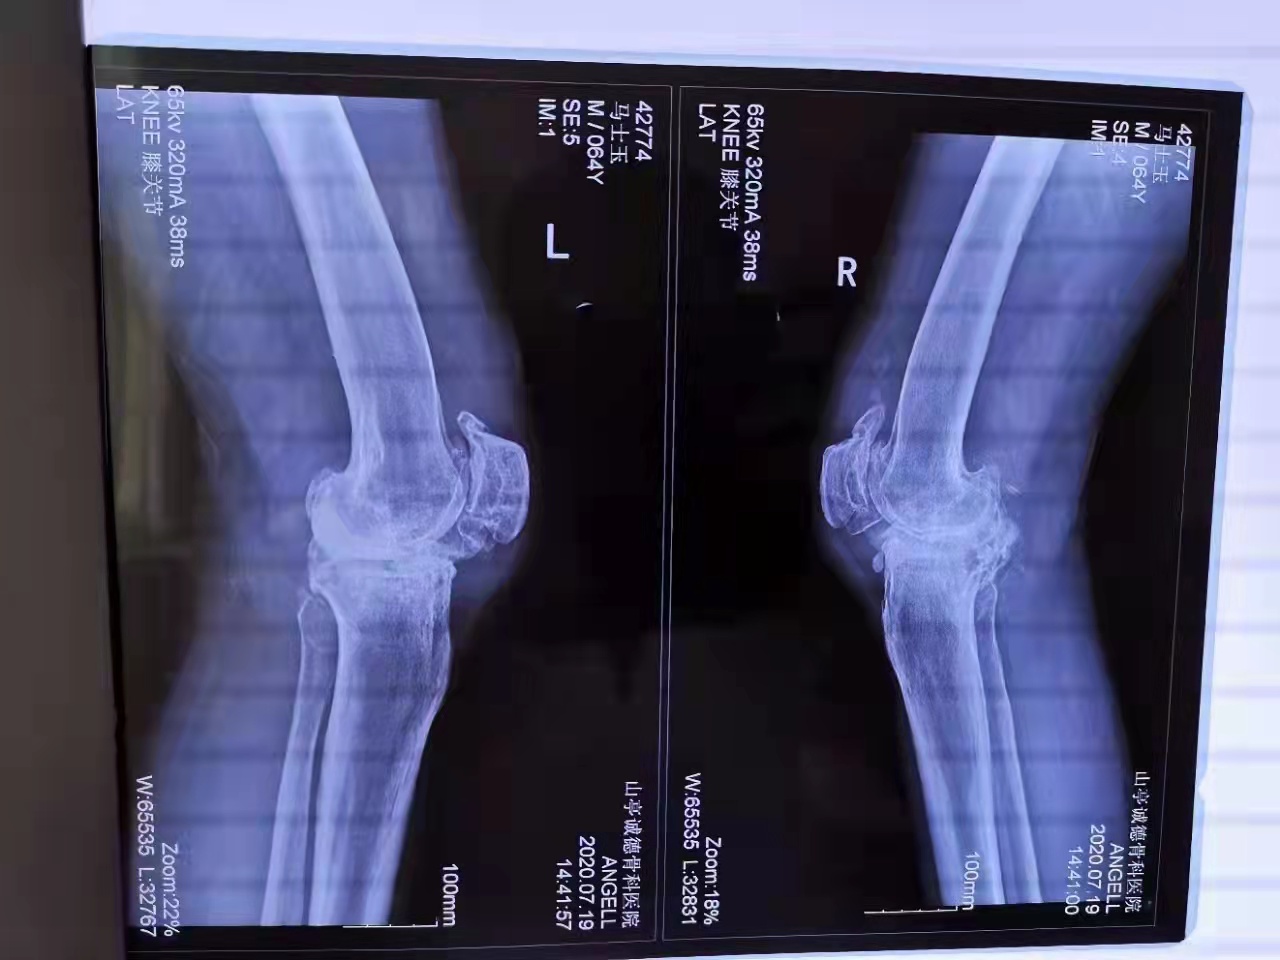

馬先生今年64歲,家住山亭區(qū)。換患雙膝關(guān)節(jié)骨性關(guān)節(jié)炎,造成下肢嚴(yán)重畸形,行走困難,疼痛難忍。在13歲時(shí)受傷骨折,沒有治療導(dǎo)致關(guān)節(jié)畸形、骨缺損。多年來傷病的困擾讓他痛不欲生。生活在困惑的黑暗中。